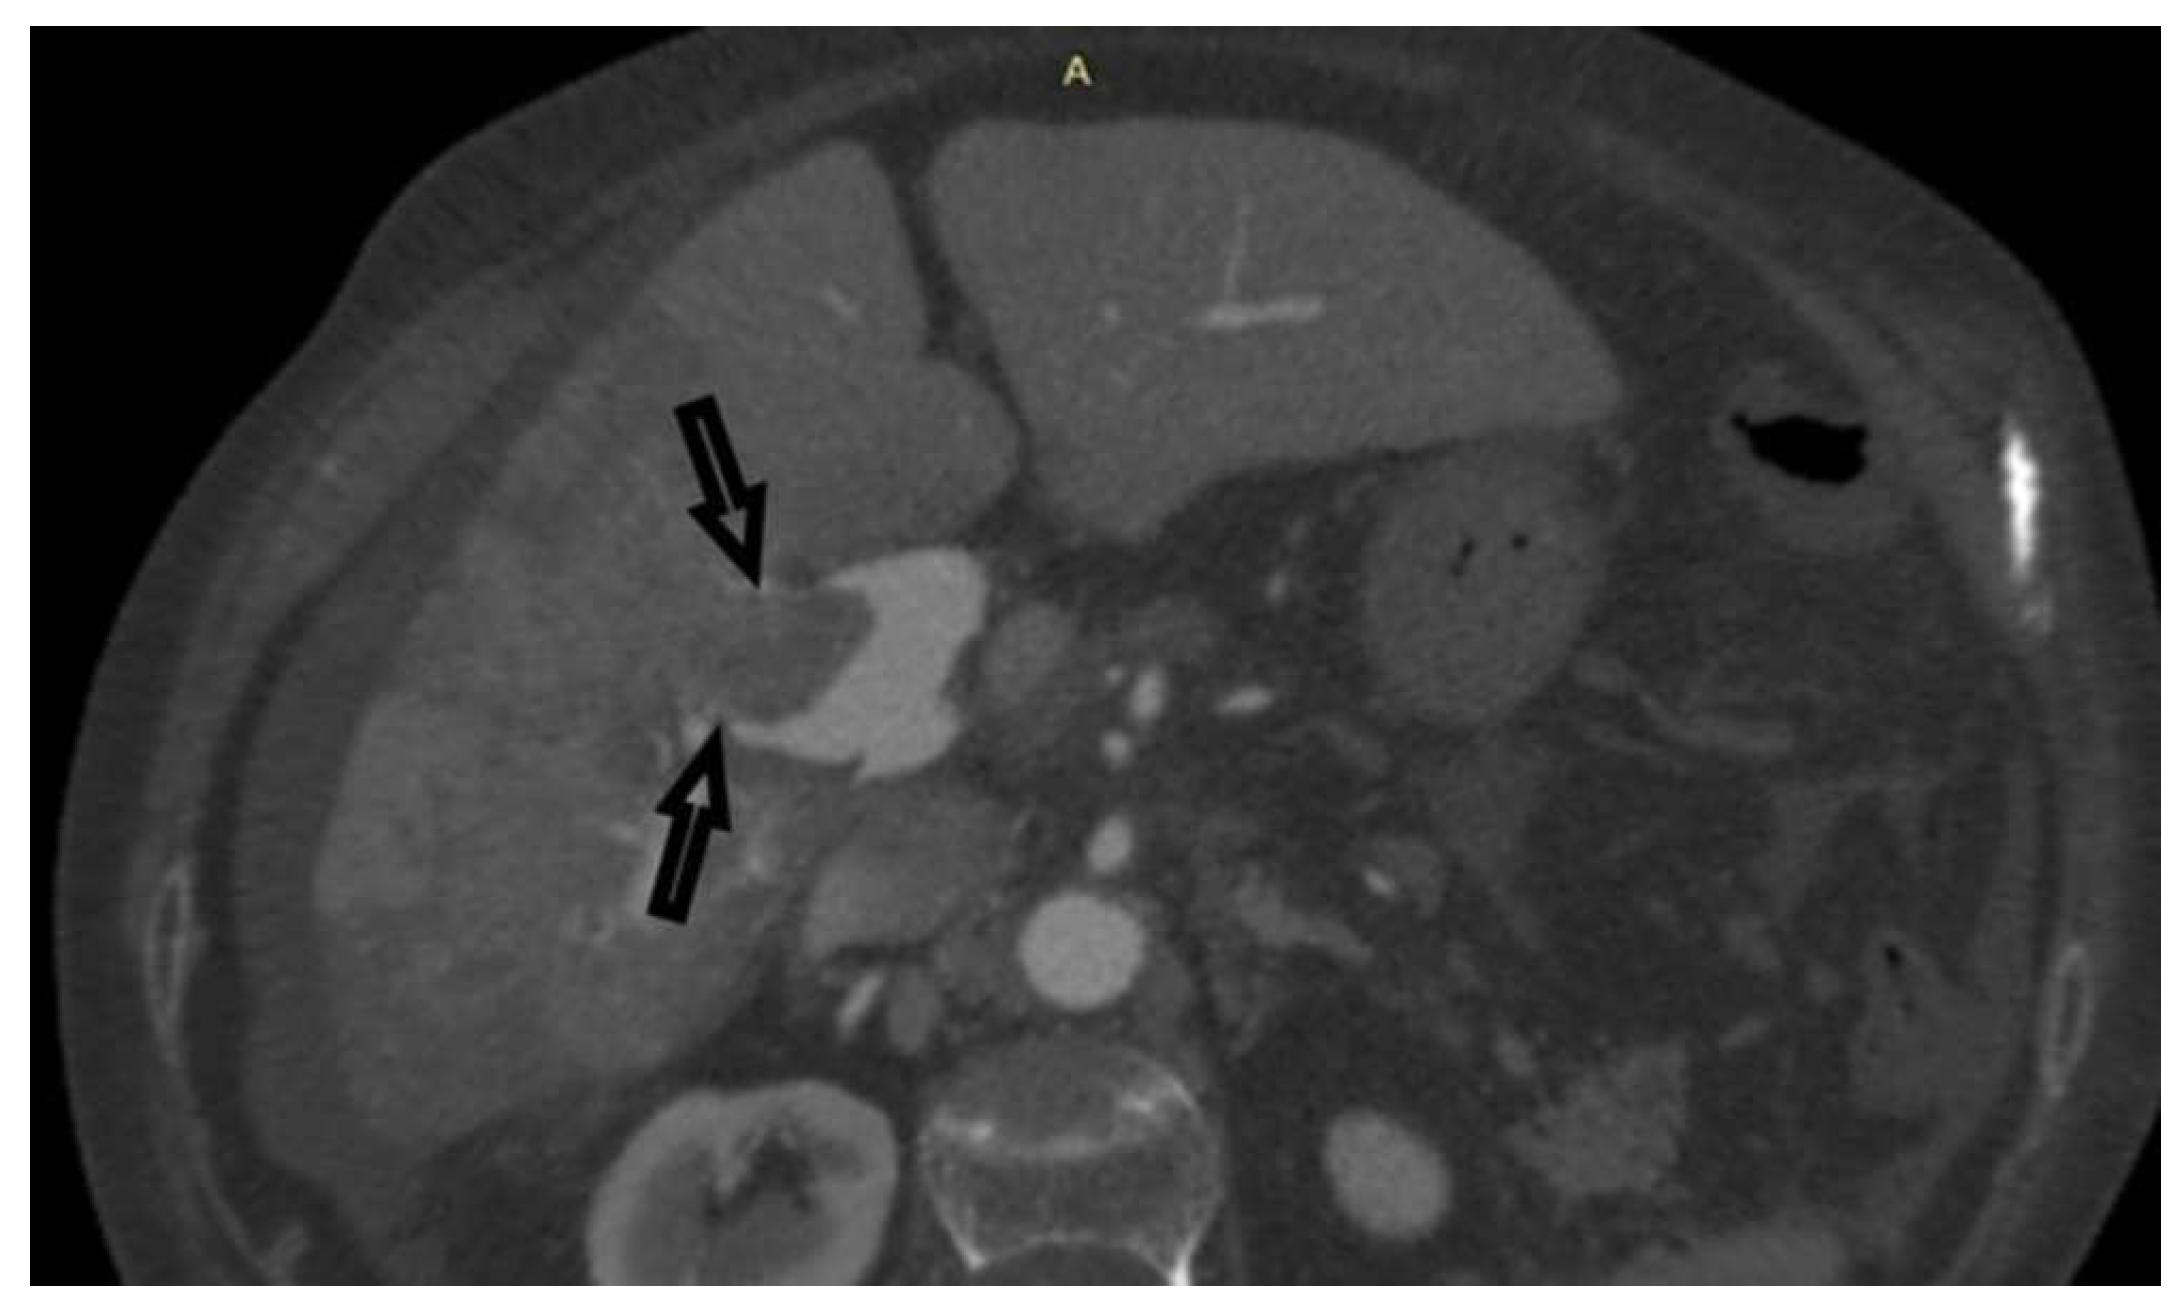

Figure 5. MDCT venous phase. The image shows rapid flushing previously in the arterial phase of hypervascular PVT, which is a finding suggestive of tumor PVT of HCC.

Case 2: A 66-year-old male was hospitalized to obtain a pathohistological verification of the existing liver lesions detected by an MDCT examination performed in a different institution. MDCT findings are dominated by a tumor PVT of the portal vein and its branches. No other signs of tumor masses could be detected. There was an apparent, intensive post-contrast enhancement in the arterial phase (a sign of neovascularization), followed by a rapid washout, highly suggestive of HCC (Figure 4 and Figure 5). AFP levels were significantly increased. Ultrasonographically, the PVT was iso-hyperechoic compared to the surrounding liver parenchyma. Using Color Doppler imaging confirmed the absence of blood flow. A CNB was performed via the anterior abdominal wall, obtaining two samples from the tumor PVT in the left portal vein. Pathohistological findings were of a moderately-differentiated HCC-a typical histological subtype (Figure 7).